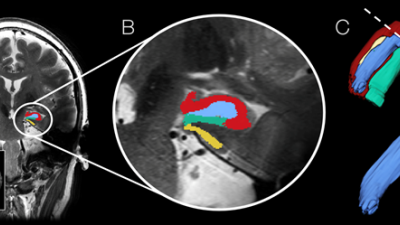

Een behandeling met electro convulsie therapie (ECT, vroeger ook vaak electroshock-therapie genoemd) bij depressie stimuleert de aanmaak van nieuwe zenuwcellen